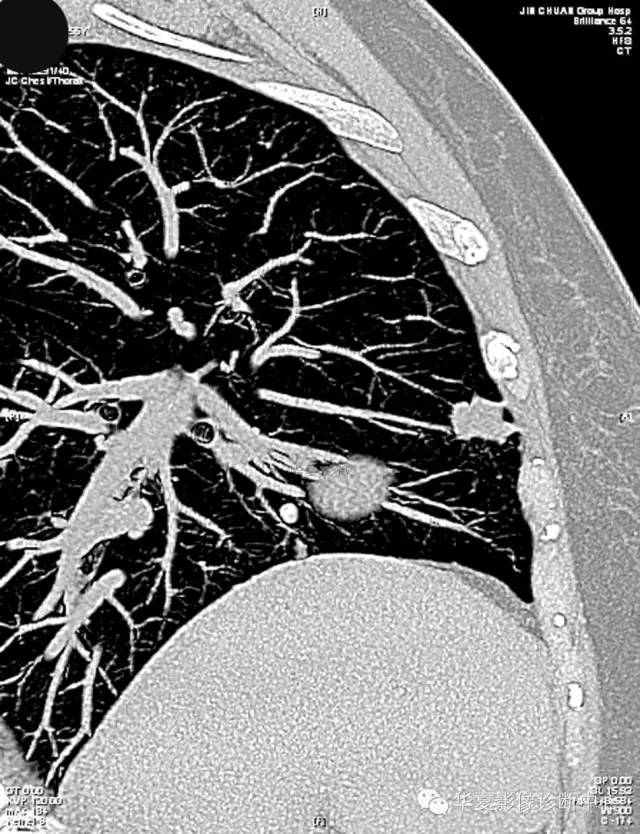

女,56岁,其父因肺癌去世,自觉胸部疼痛不适来诊要求拍胸片。

检查结论:

(右)肺中分化鳞状细胞癌。浸及胸膜。支气管残端切净。淋巴结未见癌转移(0/10)。